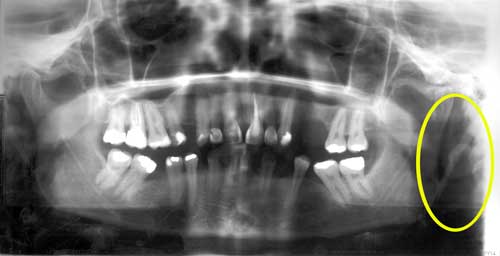

El diagnóstico del síndrome de Eagle es hecho a través de la radiografía panorámica (fig. 1) y de la tomografía computada, además del examen clínico mediante la sintomatología no patognomónica relatada por el paciente.(14,15) Balbuena et al.16 indican como rutina la radiografía cefalométrica, considerando como único inconveniente la realización de dos tomadas, pues las regiones anatómicas a ser interpretadas quedan superpuestas. La tomografía computada debe ser preferida porque ella establece la relación de los tejidos blandos y duros circunvecinos.(14) Según Sobral et al.15 podrán ser utilizados la tomografía computada y reconstrucción tridimencional (fig. 2), sin embargo, el alto costo inviabiliza su ejecución como rutina. Eso no desvaloriza completamente la radiografía panorámica, la cual es un método de examen valioso.

Fig. 1

Radiografía panorámica. Puede observarse el alargamiento y hosificación del proceso estiloide del lado izquierdo.